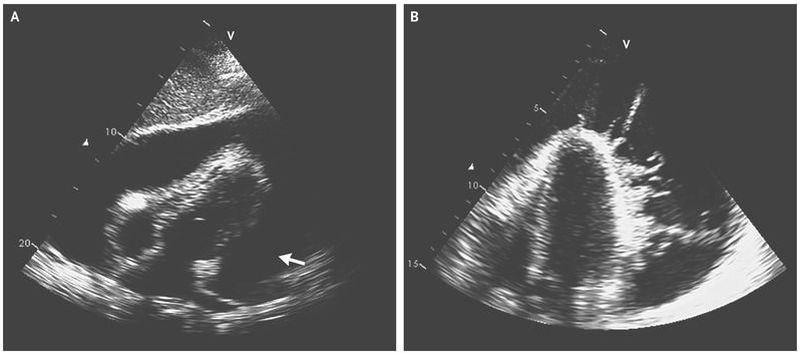

A 29-year-old woman presented to the emergency department with a 1-month history of worsening fatigue and weakness and a 2-week history of fever and dyspnea. She had emigrated from Angola 9 years before presentation. The temperature was 39.5°C, blood pressure 80/50 mm Hg, heart rate 135 beats per minute, and respiratory rate 32 breaths per minute. On examination, the patient’s neck veins were distended, and heart sounds were muffled. An electrocardiogram showed sinus tachycardia and low-voltage complexes in the limb and precordial leads. Transthoracic echocardiography revealed a large pericardial effusion with evidence of tamponade (Panel A [arrow]. The effusion contained extensive intrapericardial fibrin strands with a wormlike appearance . Pericardiocentesis was performed, and hemodynamic stability was achieved after direct aspiration of 1400 ml of purulent fluid; a pericardial drain was placed. The adenosine deaminase level in the pericardial fluid was 100 U per liter (reference range, 0 to 9), and examination of the pericardial fluid revealed acid-fast bacilli. A diagnosis of tuberculous pericarditis was made. Testing for human immunodeficiency virus was positive. The patient was treated with isoniazid, rifampin, pyrazinamide, and ethambutol for 2 months, followed by rifampin and isoniazid for an additional 4 months along with prednisolone for 6 weeks for prevention of constrictive pericarditis. Antiretroviral therapy was also initiated. The fevers resolved within the first week of treatment.